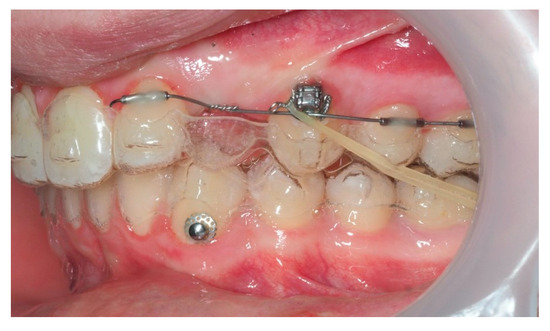

As traction progressed, the sectional appliance was extended to tooth 21 (Figure 19). A palatal button was bonded on tooth 23 to facilitate cross elastic application for vestibular movement (Figure 20). At 20 months, the bracket on tooth 23 was progressively repositioned more cervically and mesially to aid extrusion and derotation (Figure 21). A button was bonded on tooth 22 to support a wire for additional vertical anchorage. Cross elastics were also used between the palatal side of tooth 23 and buttons on teeth 33 and 34, while another elastic connected tooth 22 to 33 (Figure 22).

Figure 19.

Extension of the sectional fixed appliance up to tooth 21, with an additional tube placed on this tooth; 18 months of treatment.

Figure 20.

Palatal button on tooth 23 for cross elastic to assist in its vestibularization; 18 months of treatment.